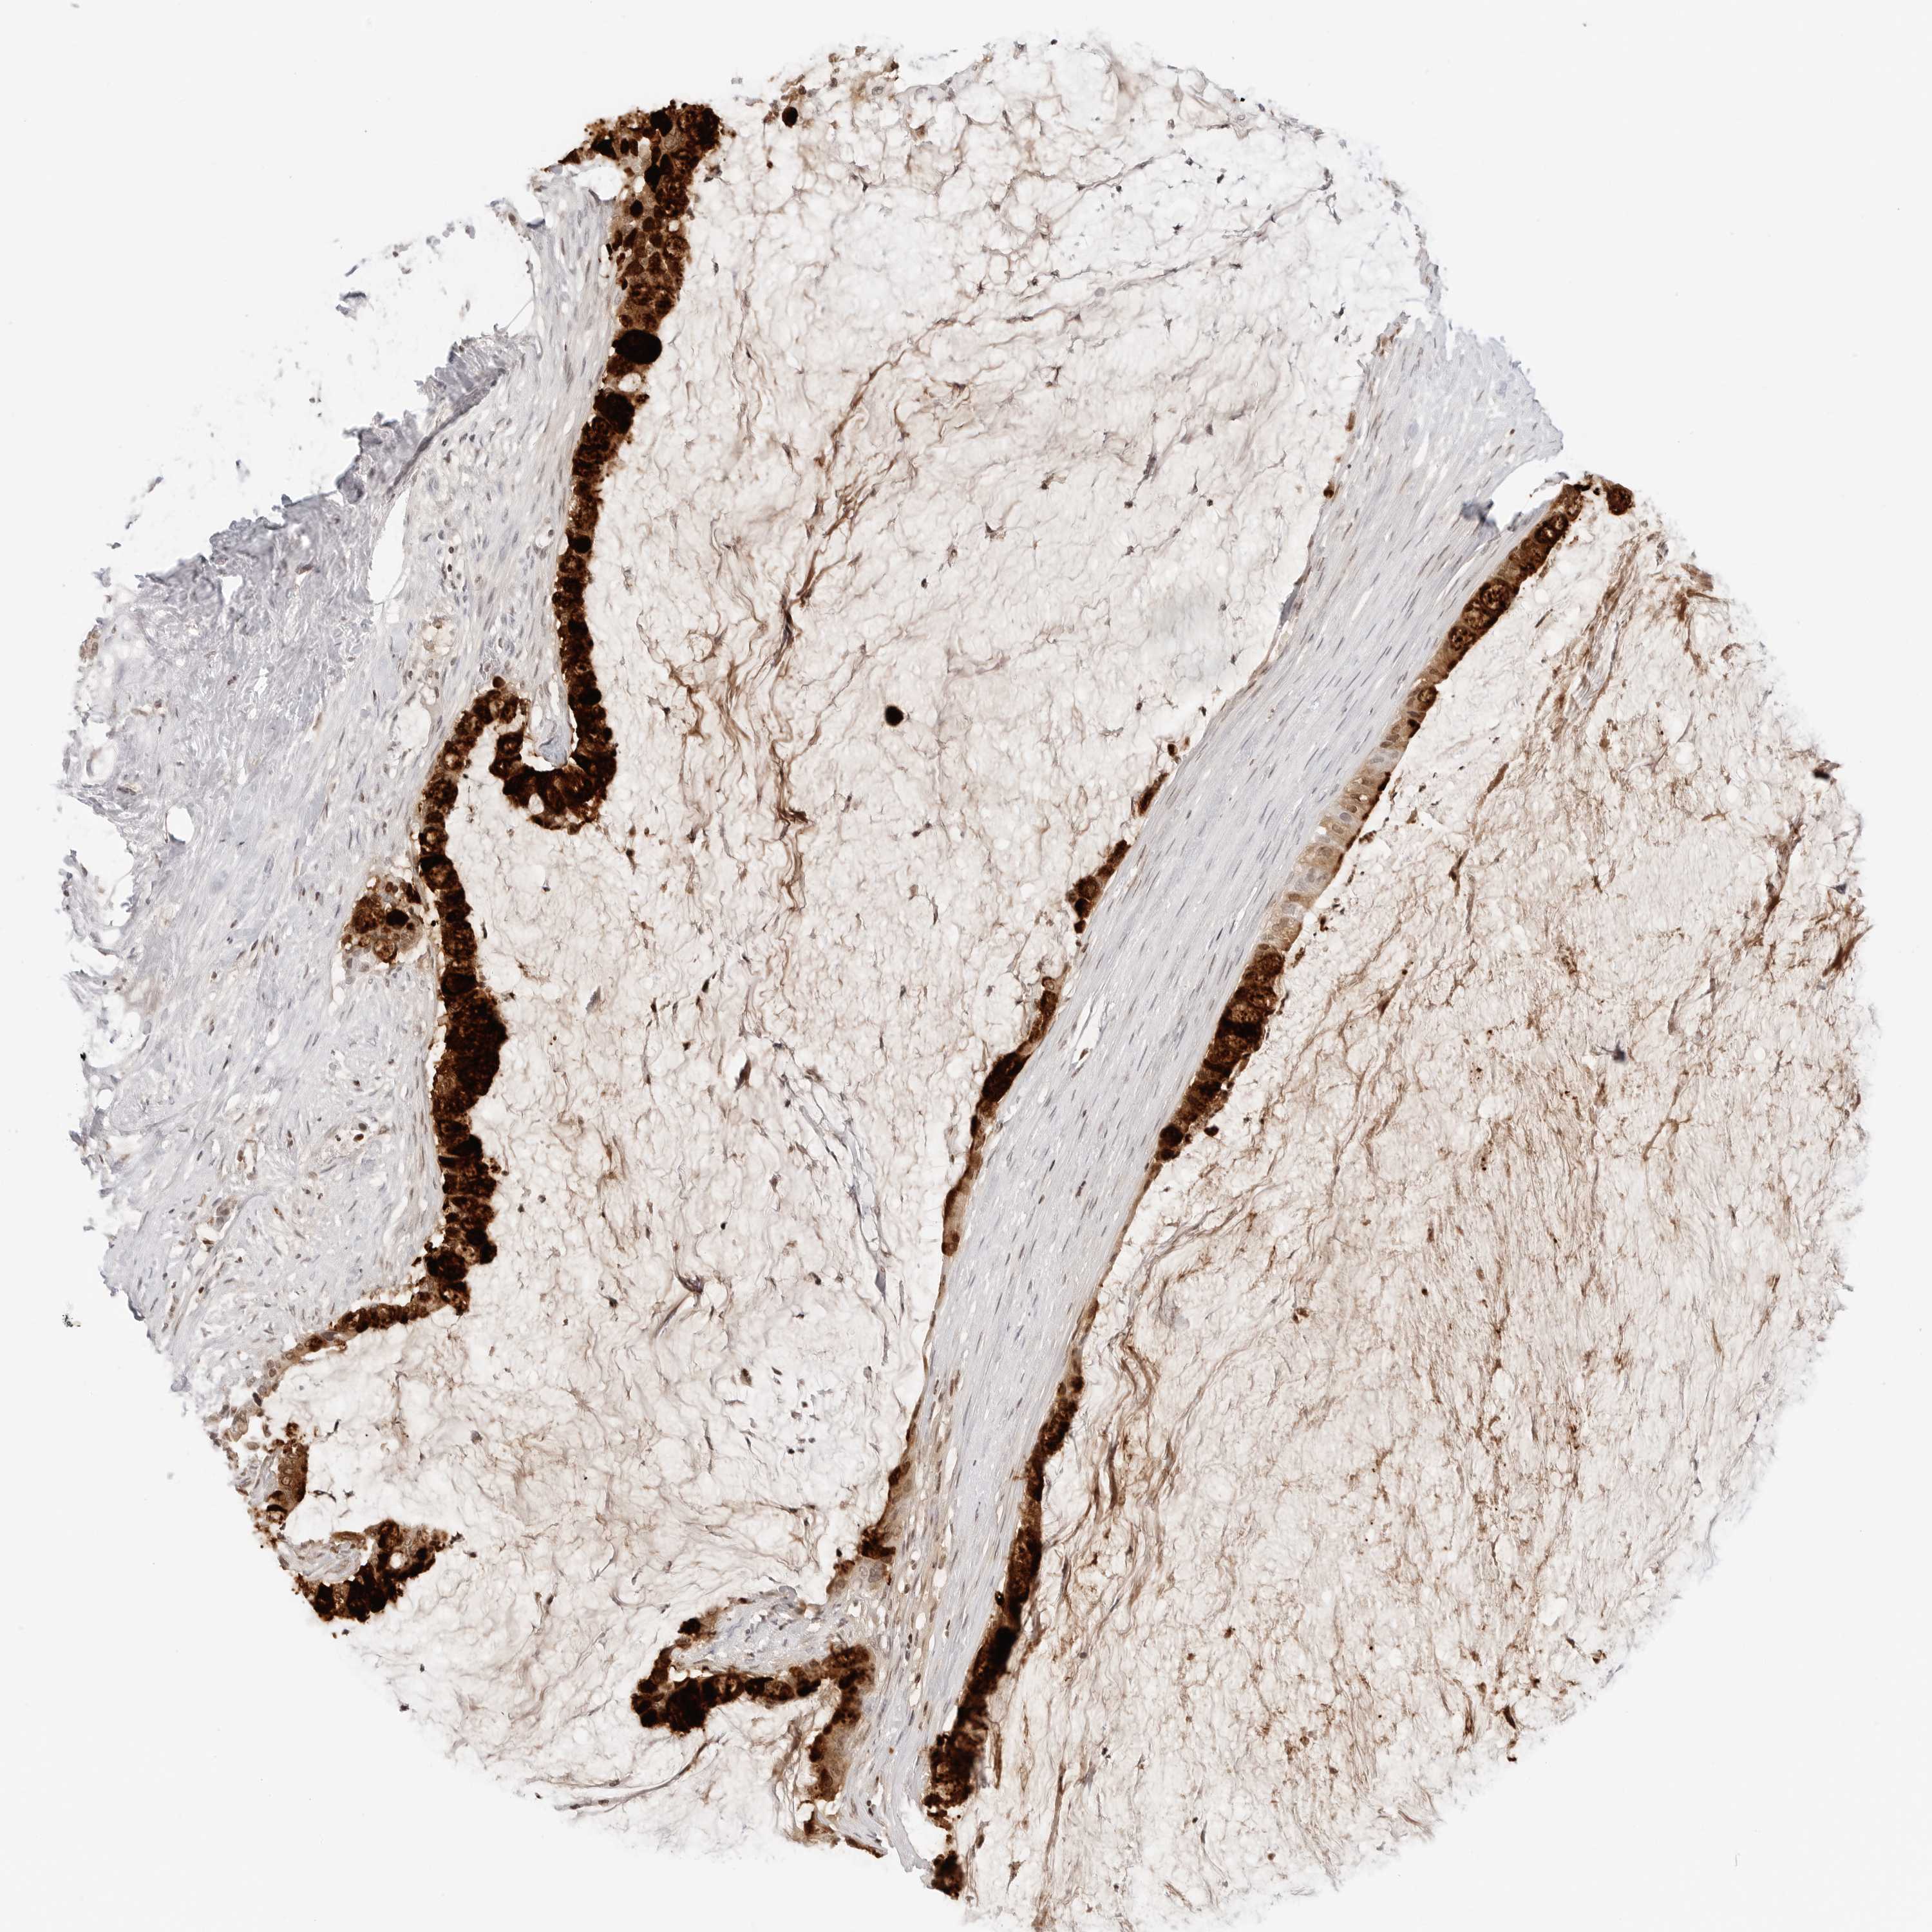

PANCREATIC CANCER - Protein expressioni

A mouse-over function shows sample information and annotation data. Click on an image to view it in a full screen mode. Samples can be filtered based on level of antibody staining by selecting one or several of the following categories: high, medium, low and not detected. The assay and annotation is described here.

Note that samples used for immunohistochemistry by the Human Protein Atlas do not correspond to samples in the TCGA dataset.

Antibody stainingi

Antibody staining in the annotated cell types in the current human tissue is reported as not detected, low, medium, or high, based on conventional immunohistochemistry profiling in selected tissues. This score is based on the combination of the staining intensity and fraction of stained cells.

Each image is clickable and will lead to virtual microscopy that enables deeper exploration of all samples and also displays staining intensity scores, fraction scores and subcellular localization as well as patient and tissue information for each sample.

Antibody HPA036705

Antibody CAB025834